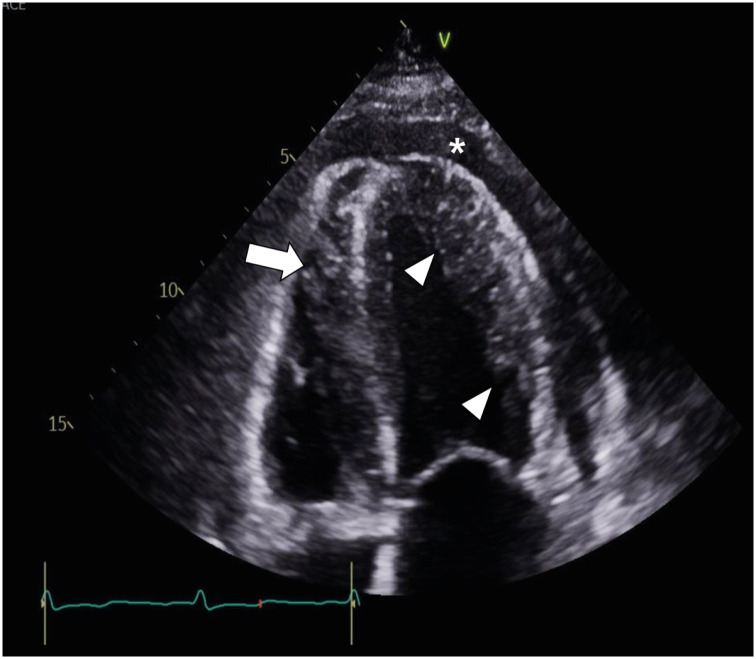

CMR参数定位有助于诊断急性淋巴细胞白血病复发时弥漫性心肌白血病浸润。

CMR Parametric Mapping Helps Diagnose Diffuse Myocardial Leukemic Infiltration in the Relapse of Acute Lymphoblastic Leukemia.